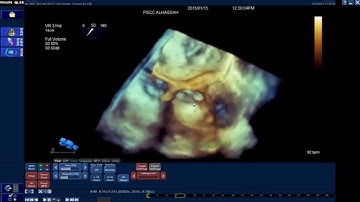

How to use Mitral Valve Quantification (MVQ) software of Q-Lab